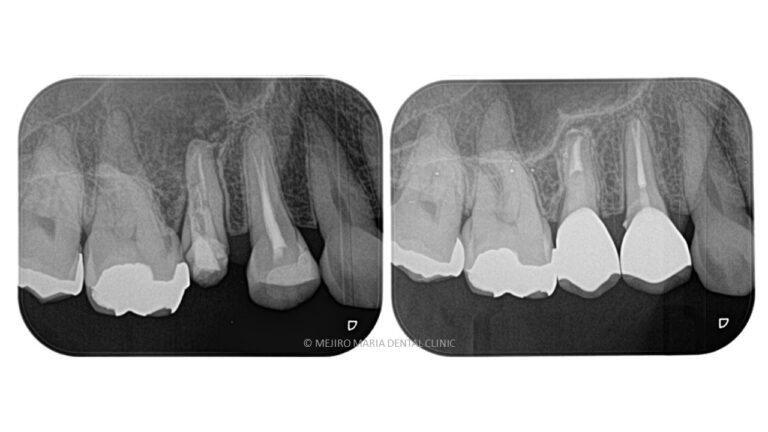

【症例】被せ物の下で進行した虫歯に対し精密根管治療で歯質を最大限に保存